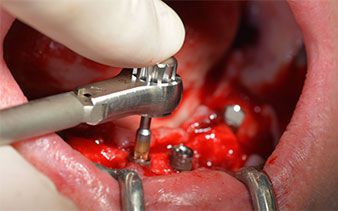

A continuación, se identificó el agujero mentoniano (foramen mentale) como la estructura anatómica límite y se alisó el cortical de la cresta ósea con la pieza de mano recta y una fresa redonda grande (fig. 4).

El protocolo quirúrgico de los implantes utilizados (SKY, bredent medical) prescribe una velocidad de 1 200/rpm para las perforaciones piloto (figs. 7-9).

Este valor se corresponde con la posición siguiente del ajuste predefinido en Implantmed. Aquí se aprecia la inclinación de aproximadamente 45 grados del contra-ángulo de W&H hacia medio caudal en la región de la pieza 45 para preservar el nervus mentalis. El foramen mentale sirve como orientación anatómica para todas las perforaciones en esta zona. Las perforaciones siguientes se realizaron con una velocidad reducida de 300/rpm (figs. 10 y 11).

El siguiente ajuste programado es la propia inserción de los implantes. En nuestra clínica, solemos insertar los implantes con una fuerza de 32 Ncm de manera estándar (figs. 12 y 13).

El requisito imprescindible para el tratamiento inmediato es una alta estabilidad primaria. Para satisfacer dicho requisito, en este caso, se prescindió del corte de rosca. La unidad de accionamiento Implantmed de W&H empleada aquí, posee un modo propio para ello que también puede seleccionarse directamente y resulta imprescindible para muchas indicaciones. Los últimos giros para la inserción del implante superaron el valor de 32 Ncm, por lo que se realizaron manualmente. En tales casos, se recomienda utilizar la función autocortante de los implantes y girar el implante varias veces hacia delante y hacia atrás de forma que el implante se aproxime gradualmente hasta su posición definitiva sin ejercer una presión excesiva sobre el hueso (fig. 14).